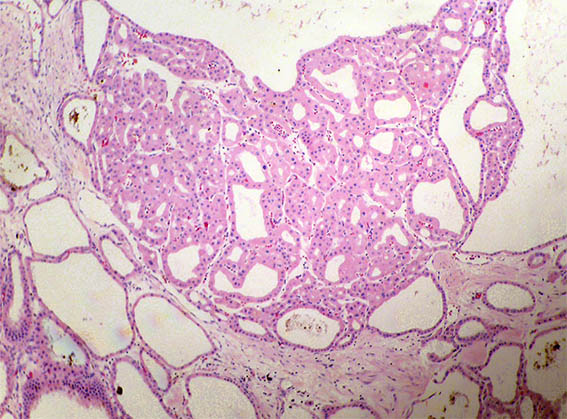

Figure 4. H&E, X100.